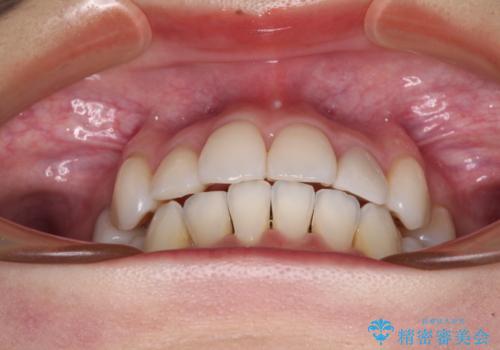

抜歯矯正は、2年半程度の治療期間を要することが一般的ですが、今回はセラミッククラウンによる補綴治療も含めて2年1ヶ月で終えることができました。

元々の歯並びが思い出せないくらい、きれいに仕上げることができました。